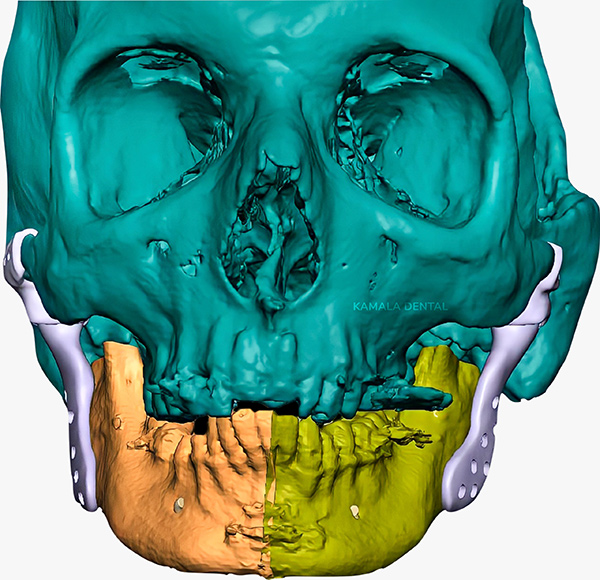

- Surgical Correction: For complex or structural joint disorders, procedures such as arthroscopy, joint reconstruction, or open joint surgery are performed with precision using advanced digital planning protocols.

- Total joint replacement: A surgical solution to restore movement and function in fused or ankylosed jaws, using custom-designed artificial joints.

Advanced diagnostic tools (3D imaging, TMJ Radiographs, digital bite analysis) to accurately identify the source of TMJ dysfunction.

- Initial Assessment & Imaging: Detailed exam and scans to evaluate jaw joints, teeth alignment, and muscle involvement.